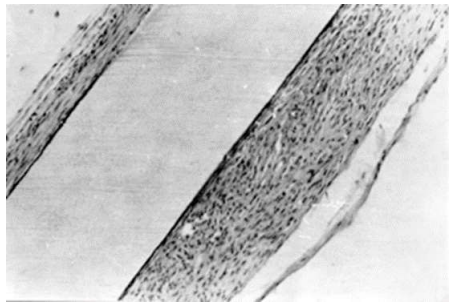

Thus, when investigating, for example, the adhesive properties of the surface of a nanomodified polymer during experimental studies, the results of “in vivo” experiments with the implantation of polymer strips treated with applied carbon-containing film (CCF) were obtained. The results of the experiment showed that 4 months after implantation of the strip treated by applying a carbon-containing coating (CCF) to its surface, connective tissue in the form of a capsule began to form around the implant plate with the treated surface, as shown in Fig.1

Fig. 1. Capsule formed around a fluoroplastic plate coated with a carbon film 4 months after subcutaneous implantation of a mouse.

Thin (a) and multilayered (b) sections of the capsule.

Magnification x 60

A capsule around the implanted fluoroplastic plate coated with CF began to form 4 months after its subcutaneous implantation in mice. Thin (a) and multilayer (b) sections of the capsule. An increase in X60 a b is a standard reaction to the biocompatibility of the implant; its thickness around the same plate varied significantly: in some areas the capsule was thin (no more than 2-4 rows of cells), in other places it looked multilayered (Fig. 1). Thin sections of the capsule consisted of young, poorly differentiated fibroblasts, sometimes in direct contact with the surface of the plate; Thin collagen fibers were found between the cells. In thick sections of the capsule, three layers can be distinguished: the inner layer (immediately adjacent to the plate), morphologically similar to the thin sections of the capsule described above; a middle layer consisting of mature fibroblasts and collagen fibers oriented parallel to the surface of the plate; the outer layer consists of fibroblasts of varying degrees of maturity and loosely arranged collagen fibers. In no case was leukocyte infiltration observed, indicating the absence of an inflammatory reaction. The described morphological picture of the capsule structure was similar in all implanted plates. Experimental studies conducted on the surface of PET, PTFE, PVDF polymers with NSS&NMS surfaces obtained using ion-plasma technology for processing the polymer surface showed that the degree of surface dispersion and the method of its modification determine the presence and effectiveness of the resulting surface characteristics, in particular: biocompatibility, antibacterial activity, lack of toxicity, presence of a developed surface with good adhesive properties for living cells. Research on nanostructured surfaces (NSS) has revealed phenomena such as tracking, correction, design and control of biological systems at the molecular level.